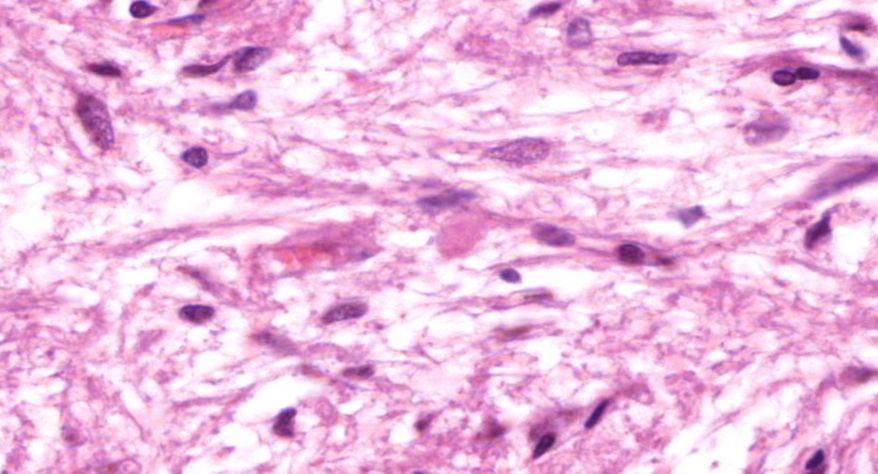

10.网状带细胞内脂褐素